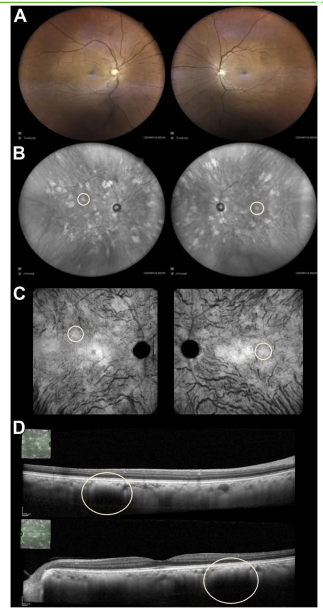

一名52岁患有神经纤维瘤病1型(NF1)的女性接受视网膜检查,检查结果如下:

右眼视力为20/30,左眼视力为20/25。

双眼超广角彩色眼底照相结果未见明显异常(图A)。

双眼超广角近红外成像显示,整个后极部及中周部散在分布着许多高反射性的与神经纤维瘤病相关的脉络膜异常(Yasunari结节)(图B)。

在深部脉络膜12×12mm平面光学相干断层扫描图像(图C)及双眼横断面光学相干断层扫描图像(图D)中,相应的脉络膜结节(以黄色圆圈标示)均呈现高反射性。